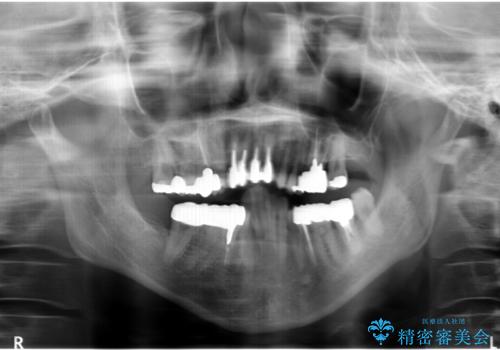

- 前歯の見た目・歯並び・銀歯の見た目の改善を求めて来院されました。

まずガタ付きの強い歯並びをマウスピース矯正インビザラインで整えたのち、セラミック治療による審美性の改善を計画します。

矯正治療が終わったのちに、精度の高いセラミックを装着することでより安定した噛み合わせとなり審美性も兼ね備えた口腔内状態で治療を終了し、今後のメンテナンスを行っていくことができます。